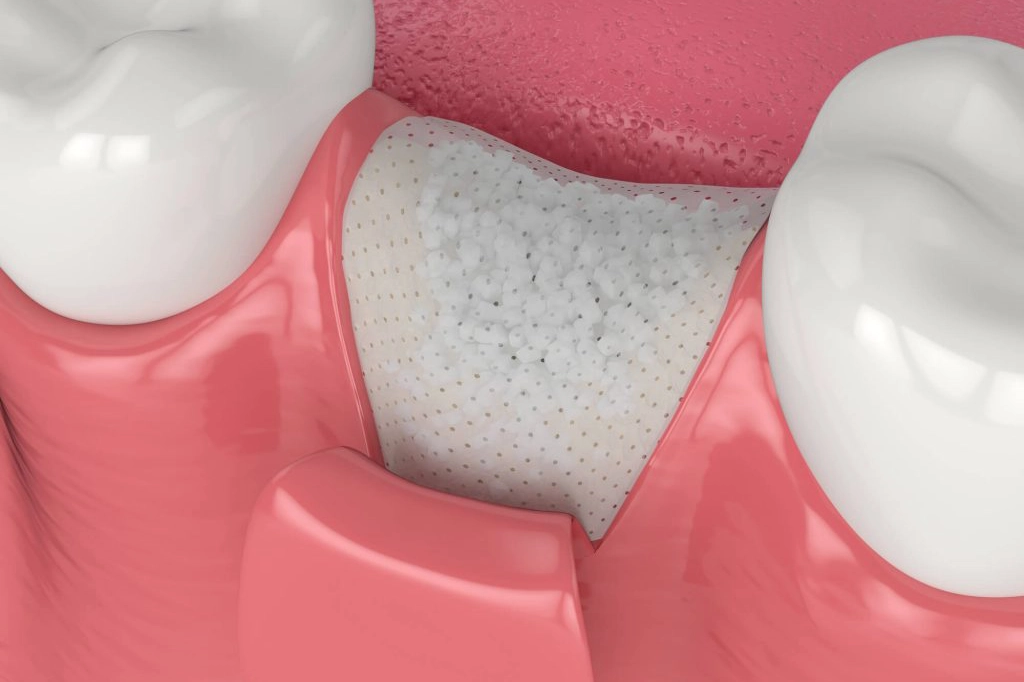

پیوند استخوان لثه، روشی است که در آن برای افزایش ضخامت و تراکم استخوان فک در ناحیهای که قرار است ایمپلنت دندان کاشته شود، از استخوانهای دیگر بدن یا پودر استخوان استفاده میشود. ایمپلنتهای دندانی پایههای فلزی هستند که در استخوان فک، جایگزین ریشۀ دندانهای از دست رفته میشوند.

برای اینکه ایمپلنت به درستی در جای خود محکم شود و عملکرد مناسبی داشته باشد، به استخوان فک با تراکم کافی نیاز دارد. در برخی موارد، استخوان فک به دلیل موارد زیر ممکن است تحلیل رفته باشد یا از ابتدا تراکم کافی نداشته باشد: